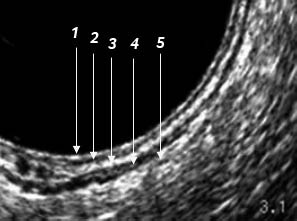

O ultrassom endorretal deve ser realizado com transdutor de alta resolução e gerar imagens de 360° para que o estudo seja circunferencial e sejam observadas com nitidez as cinco camadas da parede do reto: 1.Mucosa; 2.Muscular da mucosa; 3.Submucosa; 4.Muscular própria; 5.Gordura peri-retal.

Veja na imagem abaixo as 5 camadas:

Figura 1: Imagem adquirida com Transdutor da BK Medical modelo 2052